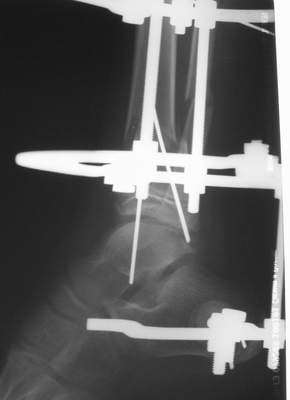

Вытяжение

Нашел в комп-ре схожий случай:

1) з/репозиция, 2) фиксация 2 спицами, 3) аппарат, 4) фиксационные

спицы удалены...

См. аттачт.